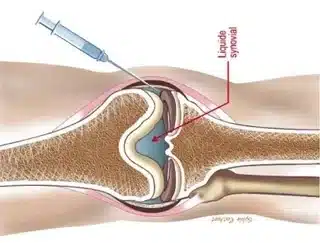

این مقاله توسط واحد تولید محتوای گروه ارتوپدی سامان، بزرگترین وبسایت ارتوپدی در ایران، تهیه شده است. آسیب غضروف زانو یک مشکل شایع در بین افراد، به ویژه افراد مسن و ورزشکاران است. غضروف بافتی نرم و لغزنده است که از استخوان ها در مفصل زانو محافظت می کند و حرکتی روان را تضمین می […]